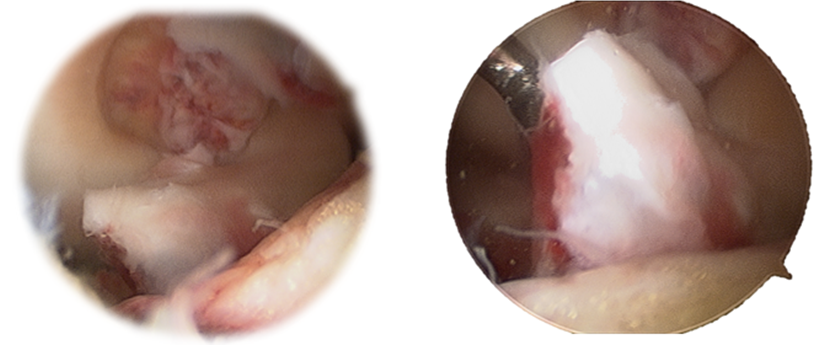

Second step- Arthroscopy was performed for tibial plateau reduction, evaluation and fixation of tibial spine avulsion fracture. A large osseous fragment was found attached to ACL (Figure 4), with no comminution. No meniscal or intermeniscal ligament tissue was found in the fracture bed. There were no meniscal nor PCL injuries. Maintaining the knee in 90º of flexion, the medial tibial spine was temporarily stabilized with K wires percutaneously and fixated with a 10mm staple trough the antero-medial portal that was created in more superior position to provide a greater angle for the introduction of the staple handle (Figure 5).

Figure 4 Arthroscopic view of avulsed LCA insertion with a large bony fragment.

Figure 5 Staple ACL arthroscopic fixation.

In this case the authors describe the use of a staple, placed arthroscopically to fixate the avulsed LCA. The medial tibial spine fracture line identified extended anteriorly up to tibial border. Therefore, the staple placed in the anterior part of fragment could not interfere with femur extension. This technique can be performed without specific arthroscopic instruments and is also an affordable option compared to the others with similar clinical and functional scores.14